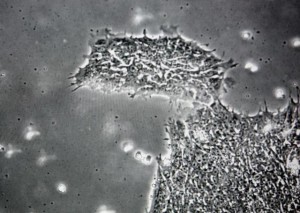

研究人員已經(jīng)發(fā)現(xiàn)了一種能夠?qū)е氯祟愓J(rèn)知減退的藻類病毒

據(jù)美國科學(xué)家稱,他們已經(jīng)發(fā)現(xiàn)了一種能夠影響人類大腦并且使我們更愚蠢的病毒。這種藻類病毒之前從未在健康人類當(dāng)中發(fā)現(xiàn),科學(xué)家發(fā)現(xiàn)它能夠影響包括視覺處理和空間意識在內(nèi)的大腦認(rèn)知功能。

約翰-霍普金斯醫(yī)學(xué)院和內(nèi)布拉斯加大學(xué)的科學(xué)家們在進(jìn)行一項(xiàng)咽喉微生物研究時(shí)偶然發(fā)現(xiàn)了這種病毒。令人驚奇的是,研究人員發(fā)現(xiàn)健康人群咽喉中的DNA與一種已知的綠藻類病毒DNA相匹配。